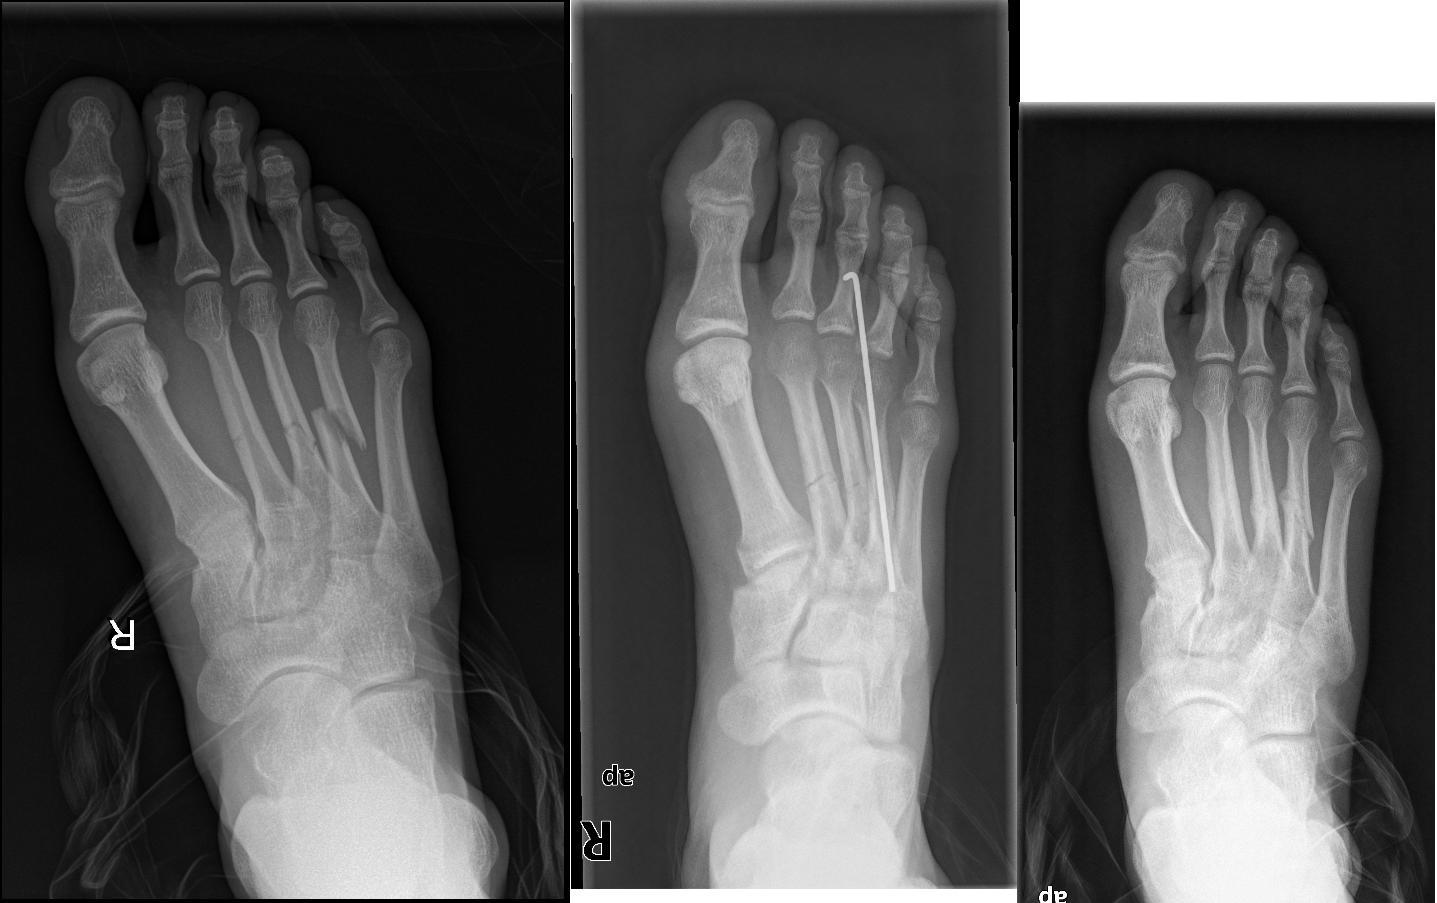

Radiografía Del Pie Fractura Del 5to Hueso Metatarsiano Foto de archivo Fractura Hueso Quinto Metatarsiano Su estructura anatómica se divide en: El quinto metatarsiano es el hueso que sufre fractura con mayor frecuencia. Esta fractura, ubicada en el hueso del pie que. Fracturas de la base del quinto metatarsiano. La fractura del quinto metatarsiano es una fractura muy habitual en la población que en la mayoría de las ocasiones se repara sin dejar ningún problema. Fractura Hueso Quinto Metatarsiano.

Radiografía del pie que muestra una fractura del quinto metatarso Fractura Hueso Quinto Metatarsiano La fractura del quinto metatarsiano es una fractura muy habitual en la población que en la mayoría de las ocasiones se repara sin dejar ningún problema secundario. Fracturas de la base del quinto metatarsiano. El quinto hueso metatarsiano es el que mayormente se fractura por alguna causa repentina (lesión ó golpe). La fractura del quinto metatarsiano es una lesión común. Fractura Hueso Quinto Metatarsiano.

Radiografía Del Pie Fractura Del 5to Hueso Metatarsiano Marker Imagen Fractura Hueso Quinto Metatarsiano Este hueso puede fracturarse en varios puntos a lo largo de su. Su estructura anatómica se divide en: Las fracturas de la base suelen denominarse como fractura de seudo jones o de la bailarina. La fractura del quinto metatarsiano es una fractura muy habitual en la población que en la mayoría de las ocasiones se repara sin dejar ningún problema. Fractura Hueso Quinto Metatarsiano.